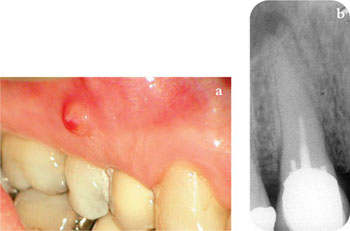

a sinus tract (Fig 1-2a) or

Fig 1-2 Signs of failure. (a) Clinical – a buccal sinus tract. (b) Radiological – a periapical radiolucent area.